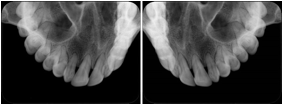

2. A patient requests cosmetic surgery to enhance their facial appearance. The case requires consultation between an orthodontist in New York and an oral surgeon in California. The cephalometric series of 2D projections constructed from a volumetric CT data set that is used for the discussion is arranged by a Structured Display for transfer between the two practitioners.

Cephalometric Series Structured Display

Figure OO-2. Cephalometric Series Structured Display